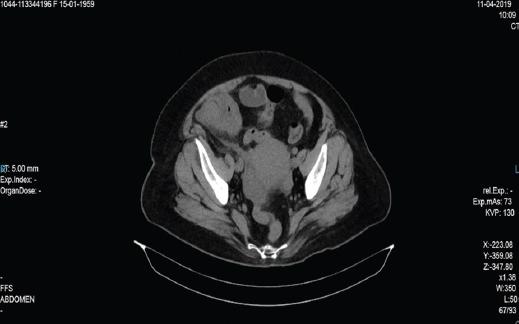

Mujer de 60 años, con antecedentes de diabetes tipo 2 e hipertensión arterial sistémica; niega antecedentes quirúrgicos. Inicia su padecimiento actual un día antes de su valoración con dolor de tipo cólico en el hipocondrio derecho, de intensidad 7/10 en la escala numérica del dolor, irradiado al cuadrante inferior derecho, acompañado de distensión abdominal, náusea llegando al vómito de contenido gastroalimentario en tres ocasiones, sin exacerbantes ni atenuantes; de manera ocasional, en las últimas 12 horas se presentó con dolor de tipo punzante, de intensidad 10/10 en la escala numérica del dolor, en la región de la fosa iliaca derecha. En la exploración física, neurológicamente íntegra, cardiopulmonar sin compromiso, abdomen globoso a expensas de panículo adiposo, peristalsis aumentada en intensidad y frecuencia, doloroso a la palpación en hipocondrio derecho y fosa iliaca derecha, Murphy negativo, McBurney positivo, con presencia de masa palpable en la fosa iliaca derecha, de aproximadamente 5 × 5 cm, móvil, no adherida a planos profundos y de consistencia firme; resto sin alteraciones. Laboratorios: leucocitos 12.67 103/μl, hemoglobina 14.1 g/dl, hematocrito 44.2 %, plaquetas 367,103/mm3, neutrófilos 82%, glucosa 24.2 mg/dl, urea 32.4 mg/dl, BUN 15.0 mg/dl, creatinina 1.0 mg/dl, sodio 137.0 mmol/l, potasio 4.6 mmol/l, cloro 98.8 mmol/l, bilirrubina total 0.18 mg/dl, bilirrubina directa 0.44 mg/dl, bilirrubina indirecta 0.26 mg/dl, DHL 357 U/l, AST 15.5 U/l, ALT 10.5 U/l, fosfatasa alcalina 107 U/l, ACE 2.13 ng/ml, C1-125 87.2 U/ml y AFP 3.54 U/ml. Tomografía abdominal en fase simple: imagen sugestiva de apendicitis aguda retrocecal complicada, con acentuados cambios inflamatorios y líquido libre en hueco pélvico, con engrosamiento nodular de la pared del ciego con múltiples ganglios ileocecales y retroperitoneales (paraórticos, intercavoaórticos y retrocrurales), el mayor de 17 mm, que pudieran ser por el proceso inflamatorio por contigüidad sin poder descartar una lesión subyacente del colon (Figs. 1 y 2). Se decide su tratamiento quirúrgico abierto, durante el cual se encuentra una tumoración a nivel de ciego y colon ascendente, de aproximadamente 10 cm, de consistencia firme, con tejido inflamatorio, y perforación a nivel de tercio medio, con salida de material fecal a la cavidad, así como proceso agudo en fase II a nivel apendicular. Se realizan hemicolectomía derecha e ileostomía, y se envía la pieza a patología. Se coloca drenaje de tipo laminar de media pulgada dirigido al hueco pélvico, el cual emerge a nivel del cuadrante inferior derecho (Figs. 3 y 4).

Figura 1 Tomografía abdominal en fase simple, corte axial, en la que se aprecia una tumoración aparentemente dependiente del ciego (círculo).